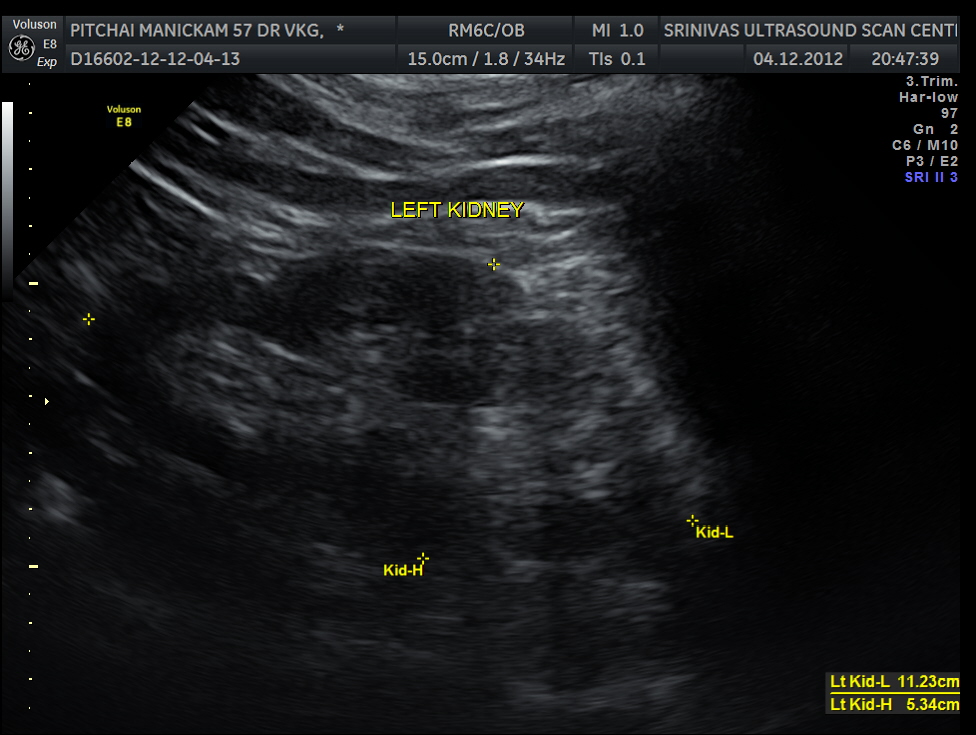

Liver, gall bladder , pancreas, spleen and the left kidney were normal . The prostate showed mild enlargement.